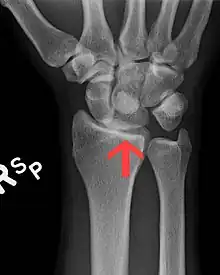

Dislocated lunate

The lunate bone is the most frequently dislocated carpal bone.